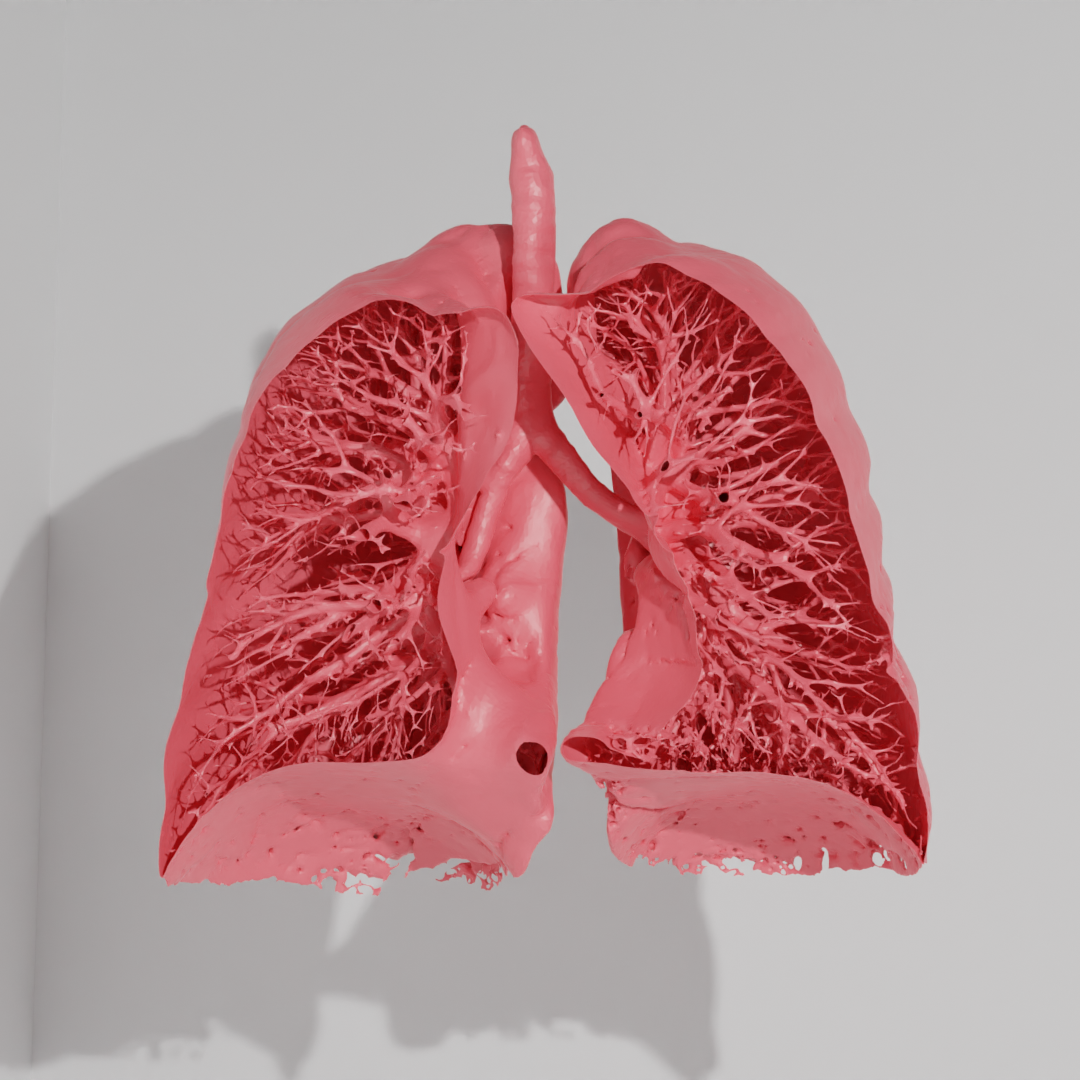

modele dróg oddechowych – projekt i wydruk 3D z żywicy epoksydowej i innych

więcej na temat projektu: UWM